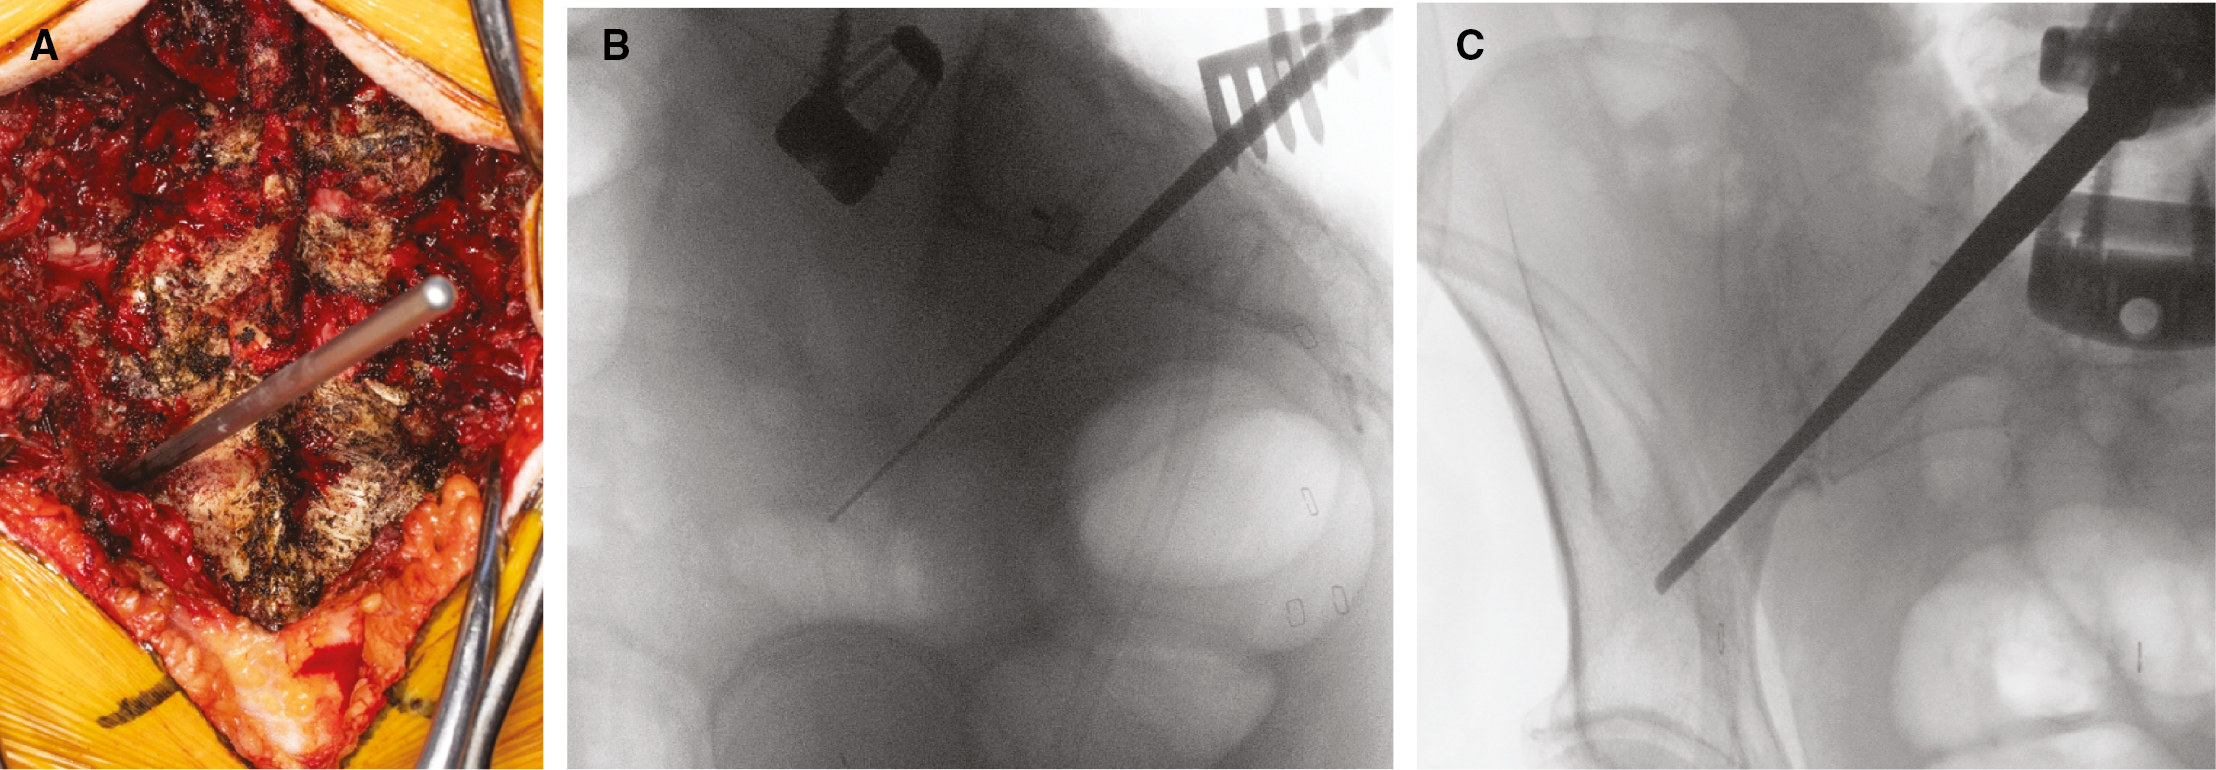

Patient positioning and surgical approach for fluoroscopic placement of S2AI screws is similar, however, with traditional C-arm fluoroscopy draped into the sterile field. Figure 3 demonstrates operating room set up and technique for fluoroscopic technique. Once exposure has been obtained at the starting point, 2-4 mm lateral and 4-8 mm inferior to the S1 foramen, an en face view of the teardrop (formed by the medial iliac wall, lateral iliac wall, and sciatic notch inferiorly) is obtained to facilitate placement of the screw (Figure 3). The screw tract is developed with either a probe or a drill under fluoroscopic visualization. The trajectory is about 40 degrees lateral and 20-30 degrees caudal and 1-2 cm above the sciatic notch directed toward the AAIS, which can be guided using fluoroscopy. AP view of the pelvis helps to visualize position in relation to the sciatic notch, and the teardrop view ensures the pathway is in the thickest part of the ilium (Figure 3).6 Once the screw trajectory is created, the walls are probed, the tract tapped, and the appropriate-sized screw placed.

Figure 3. Fluoroscopic technique for placement of S2AI screws. A) & B) Operating room set up and patient positioning with traditional C-arm fluoroscopy draped into the sterile field. C) AP view of the pelvis helps to visualize position in relation to the sciatic notch. D) En face view of the teardrop is obtained to facilitate placement of the screw. E) Screw positioning can be confirmed again on AP view of the pelvis to verify placement.